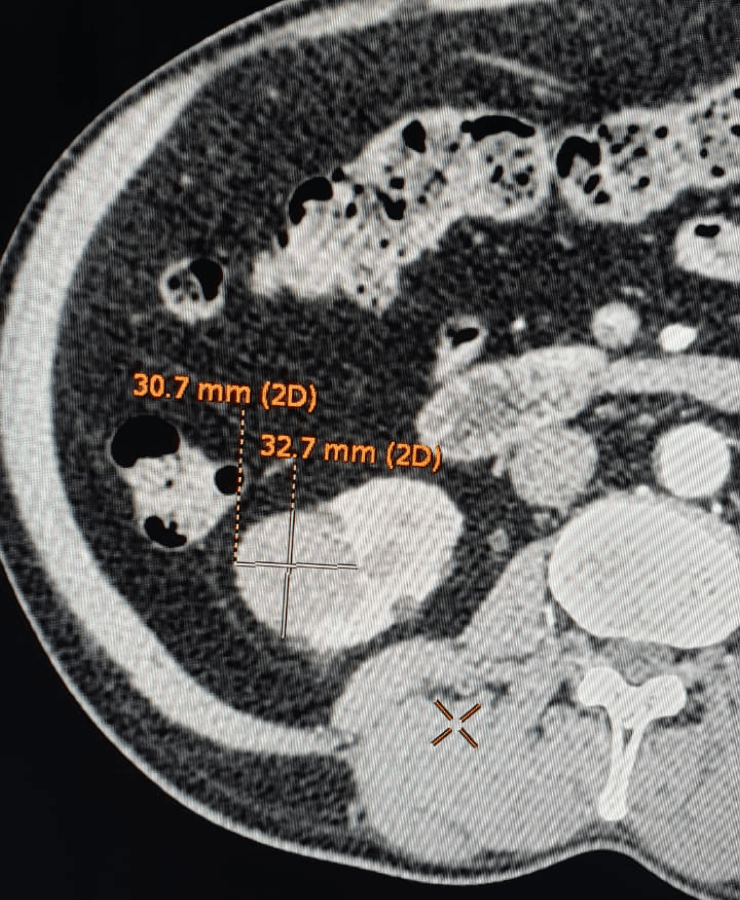

Post treatment

Many cancerous tumours of the kidney, especially small or localised lesions, can be treated by thermal ablation techniques rather than open surgery, depending on patient profile and tumour characteristics.

- Procedures are performed under USG/CT guidance to precisely target the lesion while preserving as much normal kidney tissue as possible.